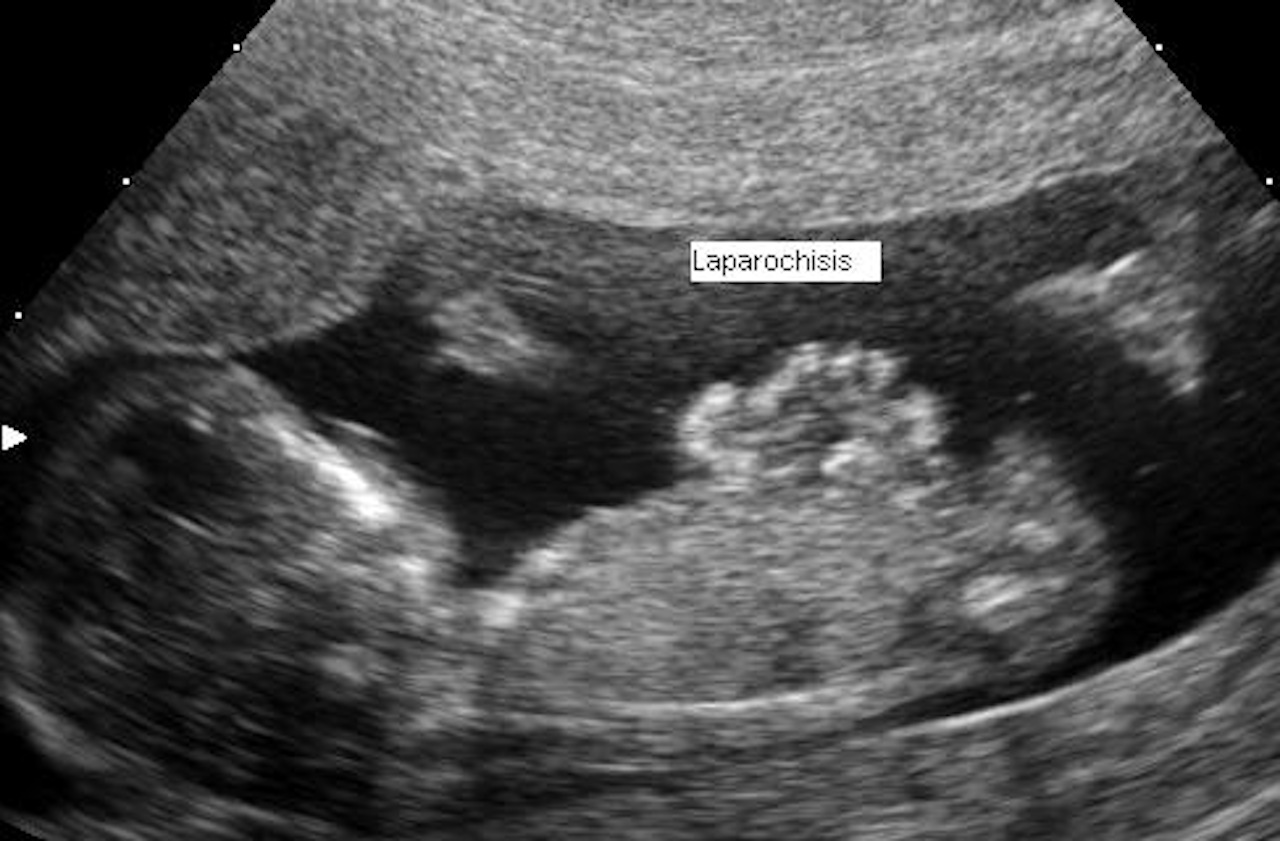

Зі зменшенням поширеності куріння серед вагітних жінок стало менше народжень дітей із гастрошизисом — патологічним розщепленням черевної стінки, крізь яке випадає кишківник і навіть інші органи. Частота цієї патології зменшилася на третину всього за сім років. Це свідчить на користь того, що кампанії з просування здорового способу життя можуть мати непередбачуваний позитивний ефект і на частоту появи рідкісних захворювань. Результати дослідження представили на конференції Американської педіатричної академії.

Науковці й раніше знали, що паління тютюну вагітною є одним із факторів появи гастрошизису в дитини, разом із молодим віком матері, інфекціями та наявністю залежностей від наркотиків. Тому вони проаналізували дані про майже 26 мільйонів пологів, щоб з’ясувати, чи зменшення поширеності паління може запобігати й поширенню гастрошизису. У дослідженій вибірці за 2017-2023 роки було понад п’ять тисяч дітей із цим станом, причому значна їх частина (майже 17 відсотків) народилася в матерів, які курили до вагітності.

За період дослідження поширеність паління серед матерів зменшилася з 9,4 до 4,1 відсотка, а частота гастрошизису — з 2,4 до 1,6 випадку на 10 тисяч пологів. Шанси на те, що дитина народиться з патологією, збільшувалися на майже 40 відсотків із кожними 10 цигарками, які матір викурювала за день ще до зачаття дитини. І хоча біологічні причини такого зв’язку до кінця не відомі, завчасна відмова матері від паління може значно зменшити ризик появи гастрошизису в дитини